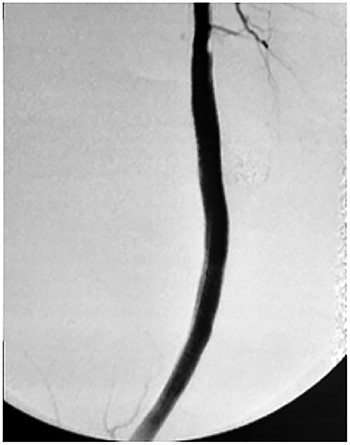

Based on the characteristics of the pseudoaneurysm, we decided on a minimally invasive interventional approach. This was in agreement with other vascular surgeons and the family. Under local anesthesia, the left common femoral artery was punctured in antegrade fashion, and an 8-F sheath was deployed. An X-ray of the popliteal region highlighted the stent fracture, and digital arteriography showed the large pseudoaneurysm. After administration of 5000 IU of heparin, a 0.035 guidewire was passed across the fractured stent and was placed distally in the posterior tibial artery. At the end of the procedure, a 7.0 × 150-mm self-expandable Viabahn endoprosthesis (W. L. Gore & Associates, Flagstaff, AZ, USA) was delivered into the stent, and adjuvant balloon inflation was performed with a 6.0 × 80-mm balloon leading to a complete exclusion of the pseudoaneurysm (Fig. 4). The final angiogram showed no residual stenosis, complete exclusion of the pseudoaneurysm, and no compromise of distal runoff. There were no complications associated with the procedure.

Viabahn endoprosthesis delivered after percutaneous intervention and immediately intraoperative angiogram.